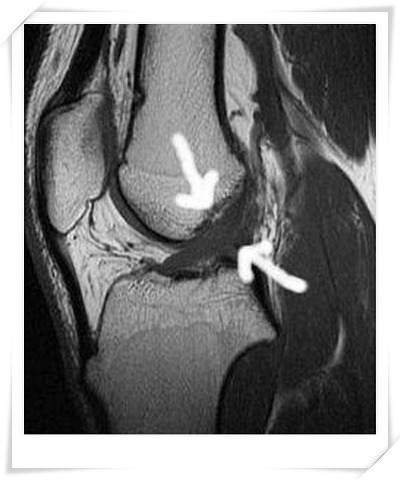

십자인대파열 증상

- 파열 당시 인대가 찢기는 느낌이 나며 '뚜두둑!'하는 소리가 납니다.

- 다리에 힘이 풀려 주저 앉게 되고 무릎에 무력감을 느낍니다.

- 몇 주정도 지나면 무릎의 동요[앞뒤 흔들림]현상이 생깁니다.

전방 십자인대파열 수술과 재활운동

슬관절 불안정성 검사인 LACHMAN 검사를 통해 무릎동요가 5mm 이상 보였다면

십자인대재건술을 시행합니다. 이때 사용하는 인대는 두 종류가 있습니다.